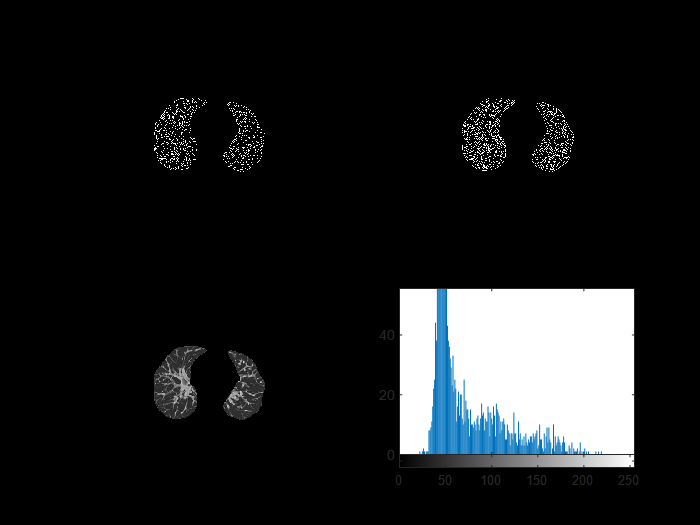

- 边缘检测

边缘检测(对比canny算子与marr-Hildreth算子) 感兴趣区域的提取可采用阈值分割方法 确定目标区域 属于编程实现范畴

%% 边缘检测

figure

I2=edge(lung,'log');

subplot(2,2,1);

imshow(I2);

title('log算子分割结果');

I3=edge(lung,'canny');

subplot(2,2,2);

imshow(I3);

title('canny算子分割结果');

Marr-Hildreth 算子(即 LOG 算子)的效果不如 Canny 算子显著,在某些情况下无法获得闭合且连续的边缘轮廓线。尽管如此,在抑制噪声的同时也会将原有的尖锐边缘变得平滑(即无法检测到这些边缘)。Canny 算子作为基于最优化理论进行推导的一种算法,在实际应用中其效果未必达到理论上的最优状态(即可能导致某些理想条件下无法实现的效果)。尽管两者都采用了高斯函数对图像进行平滑处理(即去噪),从而增强了抗噪声能力(即在去噪过程中可能会导致高频细节信息丢失),但 Canny 算子在处理高频细节方面略显不足(即可能导致部分边缘信息丢失)。此外,在检测和连接边缘时采用了多尺度检测策略,并结合方向性搜索方法以提高检测效率和准确性。

- 阈值分割

通过下列代码选择特定区域观察其直方图,确定人工选定的阈值

%% 阈值分割提取感兴趣区域

[M,N]=size(lung); %返回图像的行数和列数

subplot(223),imshow(lung), title('肺实质');

rect=getrect();

B=imcrop(lung,rect);

subplot(224);imhist(B),title('直方图');

采用阈值处理方法提取出感兴趣区域(对于手动进行直方图分析时,默认选取双峰间谷底对应的灰度级作为分割门槛),通过上述方法进行图像分割后,在形态学上能够清晰地区分出肺部血管与肺实质之间的界限。尽管该方法存在一定的误差范围,在实际应用中用于检测血管内是否存在血栓时仍需谨慎评估其准确性。